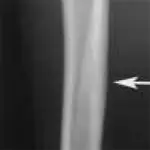

Figure 1A. Hairline fracture of the fibula.

Figure 1B. The fracture is more clearly seen 4 weeks later following bone resorption and periosteal proliferation at the fracture site.